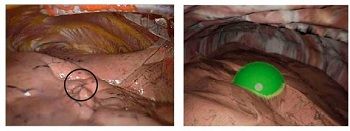

(사진 : 폐결절 위치를 나타낸 실제 흉강경 영상 및 시뮬레이션 영상 캡처)

이 특허 기술은 환자의 CT 영상을 기반으로 실제 수술 환경과 유사한 무기폐 3D 모델을 생성한 뒤 폐결절의 위치와 절제 범위를 시각화해 영상으로 출력해주는 시스템이다.

수술 전 시뮬레이션 영상을 확인할 수 있고, 수술 중에도 실제 흉강경 영상과 비교할 수 있다.